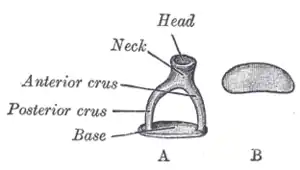

Description

L'étrier est le plus petit et le plus léger des os du squelette avec une longueur de 2,6 à 3,4 mm et un poids de 2 à 4,3 mg.

Il est situé dans la cavité tympanique et se positionne horizontalement entre le processus lenticulaire de l'enclume et la fenêtre du vestibule.

De l'extérieur vers l'intérieur, l'étrier comporte une tête qui se divise en deux branches antérieure et postérieure. Les extrémités médiales des deux branches sont reliées par une base. Ses mouvements sont éventuellement amortis par le muscle stapédien. Les branches sont excavées en gouttière et constituent la superstructure de l'étrier qui relient la tête et la platine. La platine est une mince lame osseuse ovoïde, qui s'impacte dans la fenêtre ovale du vestibule.

L'étrier mesure chez l'humain 3 mm de large et 4 mm de haut, et pèse entre 2 et 4,3 mg. Il est couché horizontalement. Il s'articule en dehors avec l'enclume, en dedans avec le labyrinthe osseux de l'oreille interne par la fenêtre ovale.

Tête de l'étrier

La tête de l'étrier (ou tête du stapès) a une forme cubique aux angles arrondis.

Elle possède sur sa face latérale une cavité glénoïde recouverte de la facette articulaire de la tête de l'étrier répondant à la facette articulaire du processus lenticulaire de l'enclume. Ces deux facettes constituant l'articulation Incudo-stapédienne.

Son bord antérieur est lisse, alors que le bord postérieur est creusé de deux petites cavités servant d'insertion au tendon du muscle stapédien,

Branches antérieure et postérieure de l'étrier

De la face interne de la tête naissent les deux branches antérieure et postérieure qui se dirige médialement en s'écartant respectivement vers l'avant et vers l'arrière et formant une arche concave en dedans. L'arche est fermée en dedans par la base.

Les branches sont concaves vers l'intérieur de l'arche. La branche antérieure est plus courte et plus droite que la postérieure.

L'espace entre les deux branches est de taille et de forme variable. Il est obturé par la membrane stapédiale. Il laisse parfois passer un vaisseau grêle, vestige de l'artère stapédienne.

Base de l'étrier

La base de l'étrier (ou base du stapès ou sole de l'étrier ou platine de l'étrier) est une mince lame osseuse qui relie les extrémités médiales des branches antérieure et postérieure. Elle est de forme ovalaire et s'adapte à la fenêtre vestibulaire.

Son bord supérieur est légèrement convexe et son bord inférieur est plus rectiligne, ou concave.

Sa face tympanique externe est légèrement excavée. Sa face vestibulaire interne est plate ou faiblement convexe et recouverte d'un cartilage.

Elle est maintenue dans la fenêtre par le ligament annulaire de stapès.